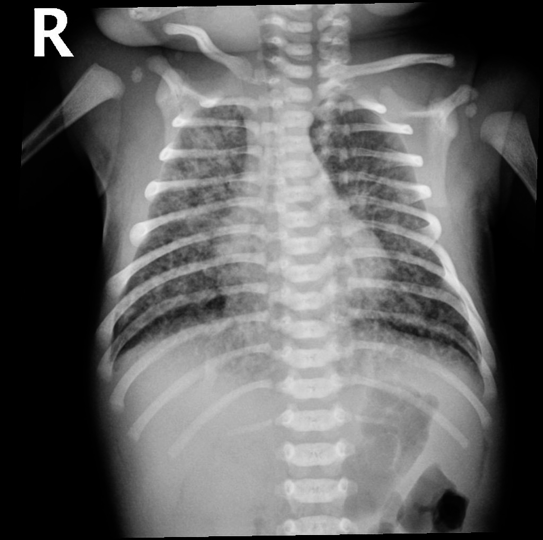

Meconium Aspiration Syndrome

Pulmonary sequelae: Higher incidence of pneumonia, hyperinflation, consolidation, patchy infiltrates. If severe, air leak and pneumomediastinum may occur.

- Hyperinflation,

- Consolidation,

- Patchy infiltrates

- If severe, air leak and pneumomediastinum may occur